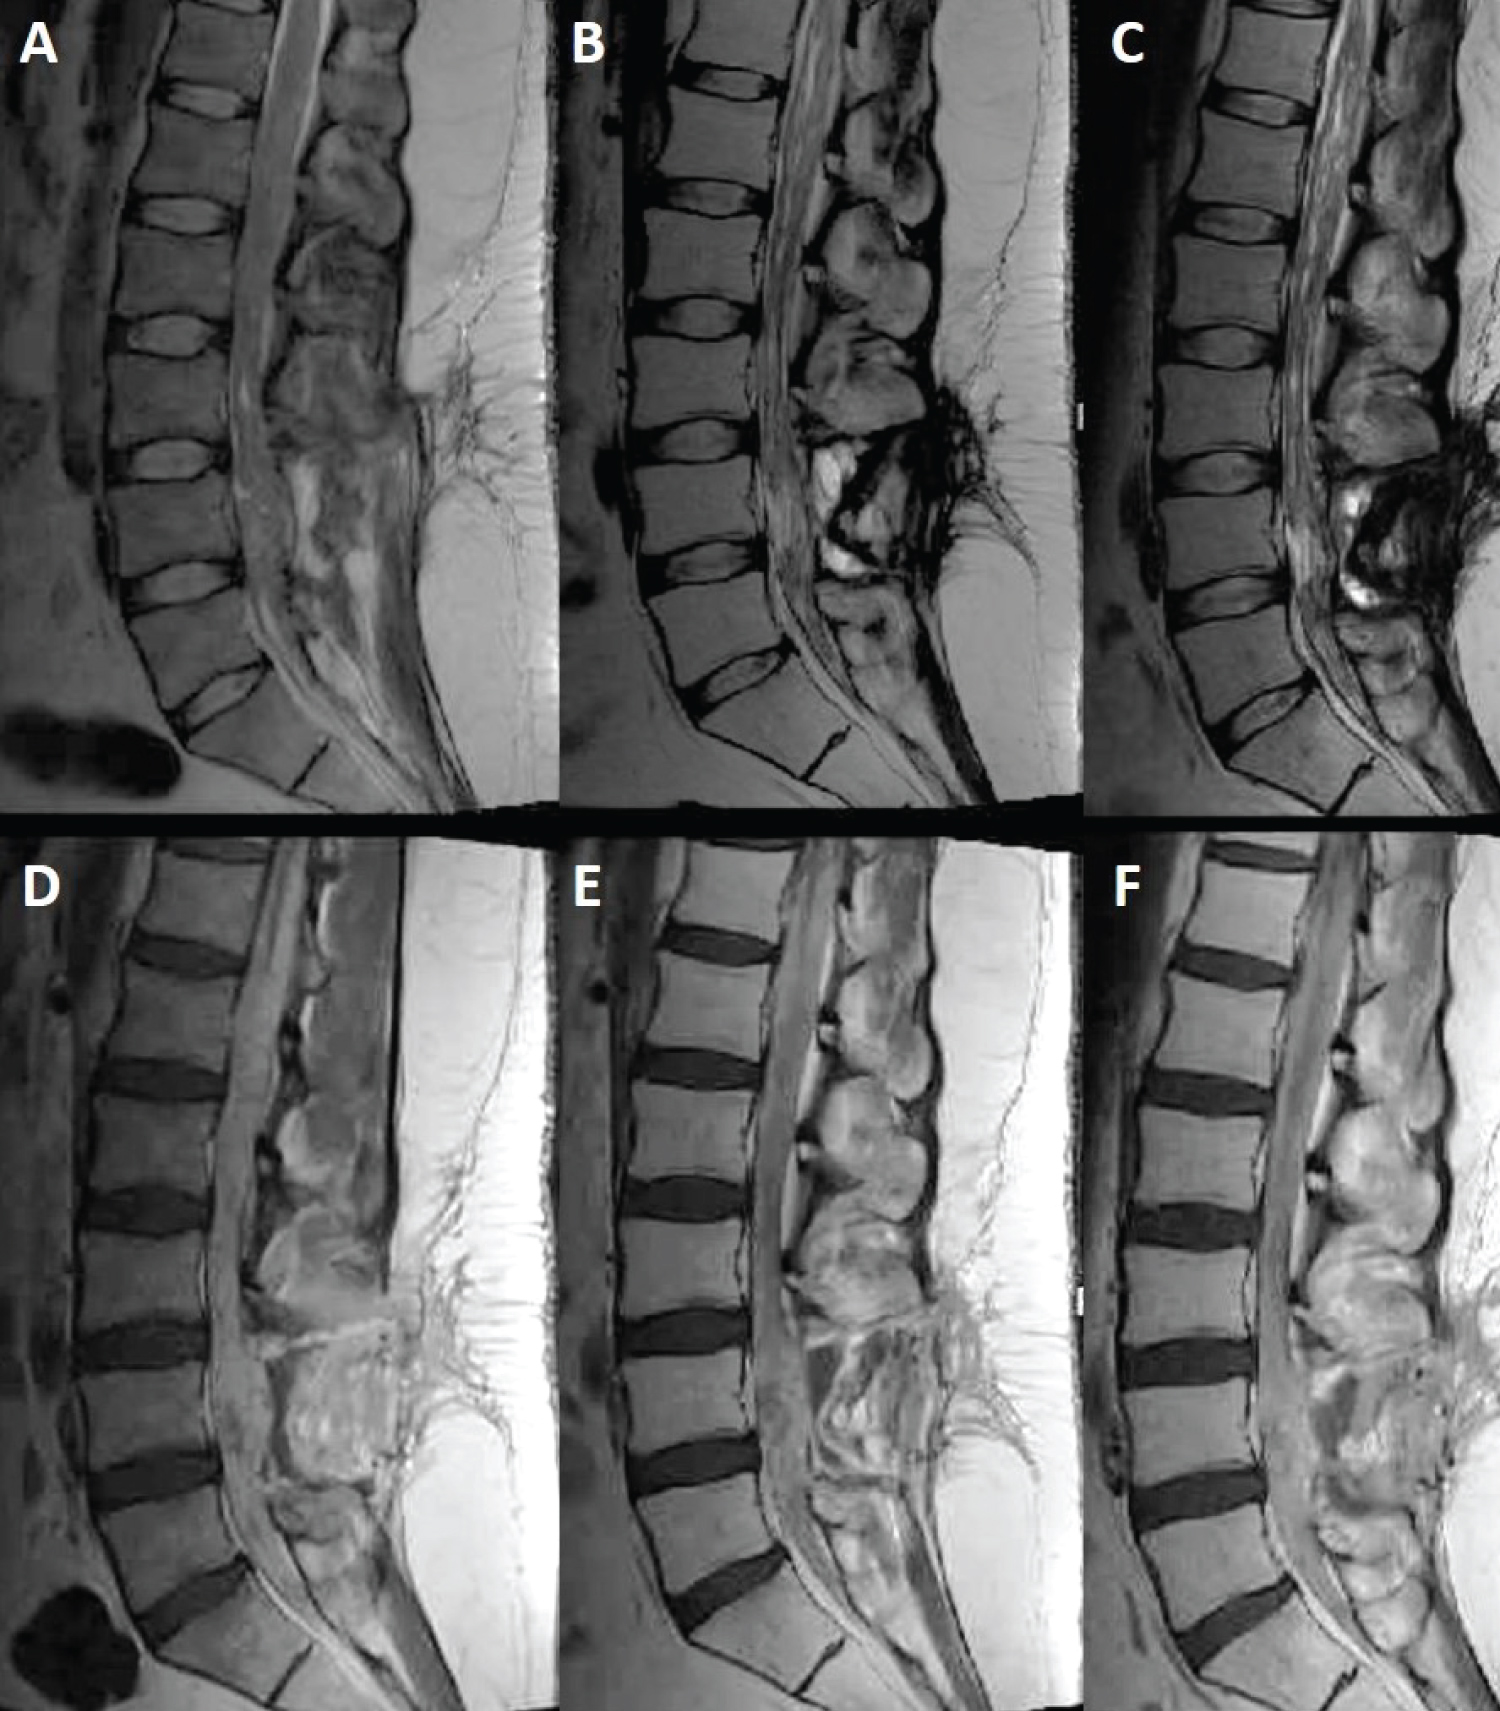

Within the first month postoperatively, the patient developed positional headaches and vision changes, especially in the left eye. Evaluation per neuro-ophthalmology identified papilledema, retinal hemorrhage, and worsening left eye exotropia. Repeat imaging revealed marked progression of thoracic and lumbar disease with no change in cervical or medullary foci (Figure 2). Spinal enhancement filled the dural space, obscuring the nerve roots and the tip of conus medullaris. Additionally, an intrathecal arachnoid cyst was noted to compress the spinal cord from T4 to T8, resulting in edema from T8-T11.

Figure 2: Sagittal T2 (top row) and T1 post-contrast (bottom row) MRI sequences demonstrating lesion progression at 1 month (A,D), 4 months (B,E) and 6 months (C,F) post-operatively. View Figure 2